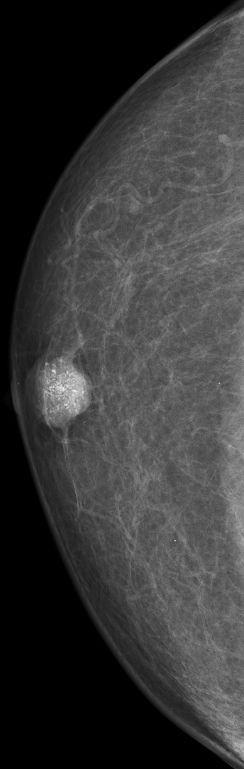

| DCIS | 80-jähriger Mann mit einem Knoten rechts retromamillär. Mammographie: Dichter Knoten mit multiplen Mikroverkalkungen unmittelbar periareolär. Histologie: papilläres DCIS, G2, 19 mm, ER: 12/12, PR: 6/12, Ki-67: 20%. Th.: Exzision, Radiatio der Mamma, TAM über 5 Jahre | ||||

rechts CC![]() |